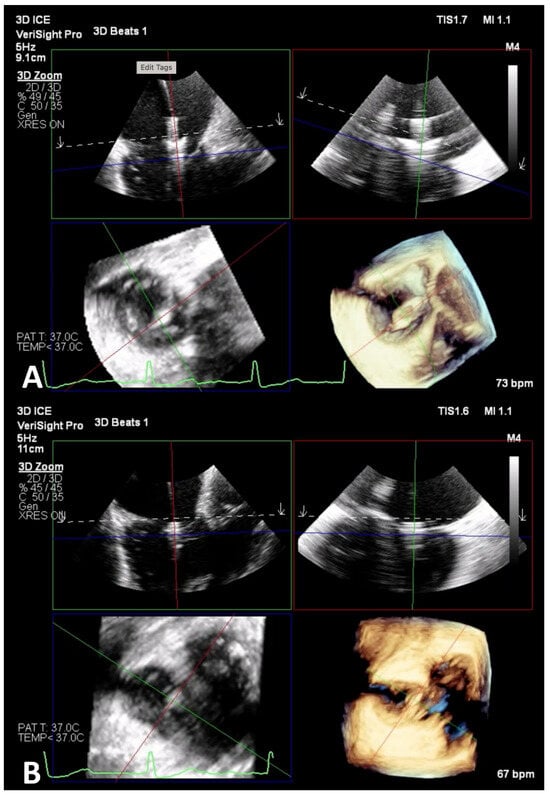

6.2. ICE-Guided TEER